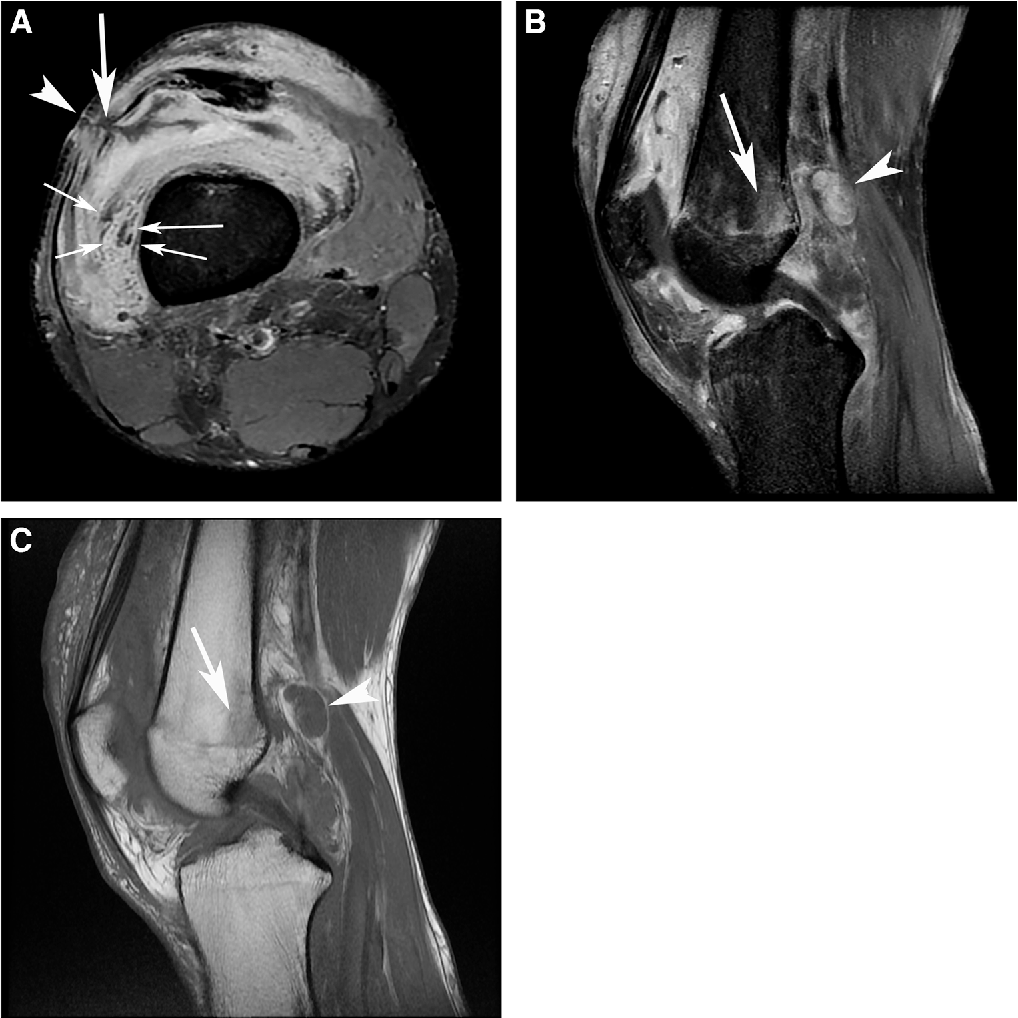

Synovitis of the knee following a highpressure injection injury with Hydraulic Oil Injection Injury Surgery is required to relieve pressure in “compartments” of the hand and forearm in order to preserve blood flow and also to remove the injectate and damaged tissue. Hydraulic injection injury occurs when the outer layer of skin is broken by a jet of fluid under pressure. How hydraulic injection injuries damage. If edema is significant, consider administering 100 mg. Hydraulic Oil Injection Injury.